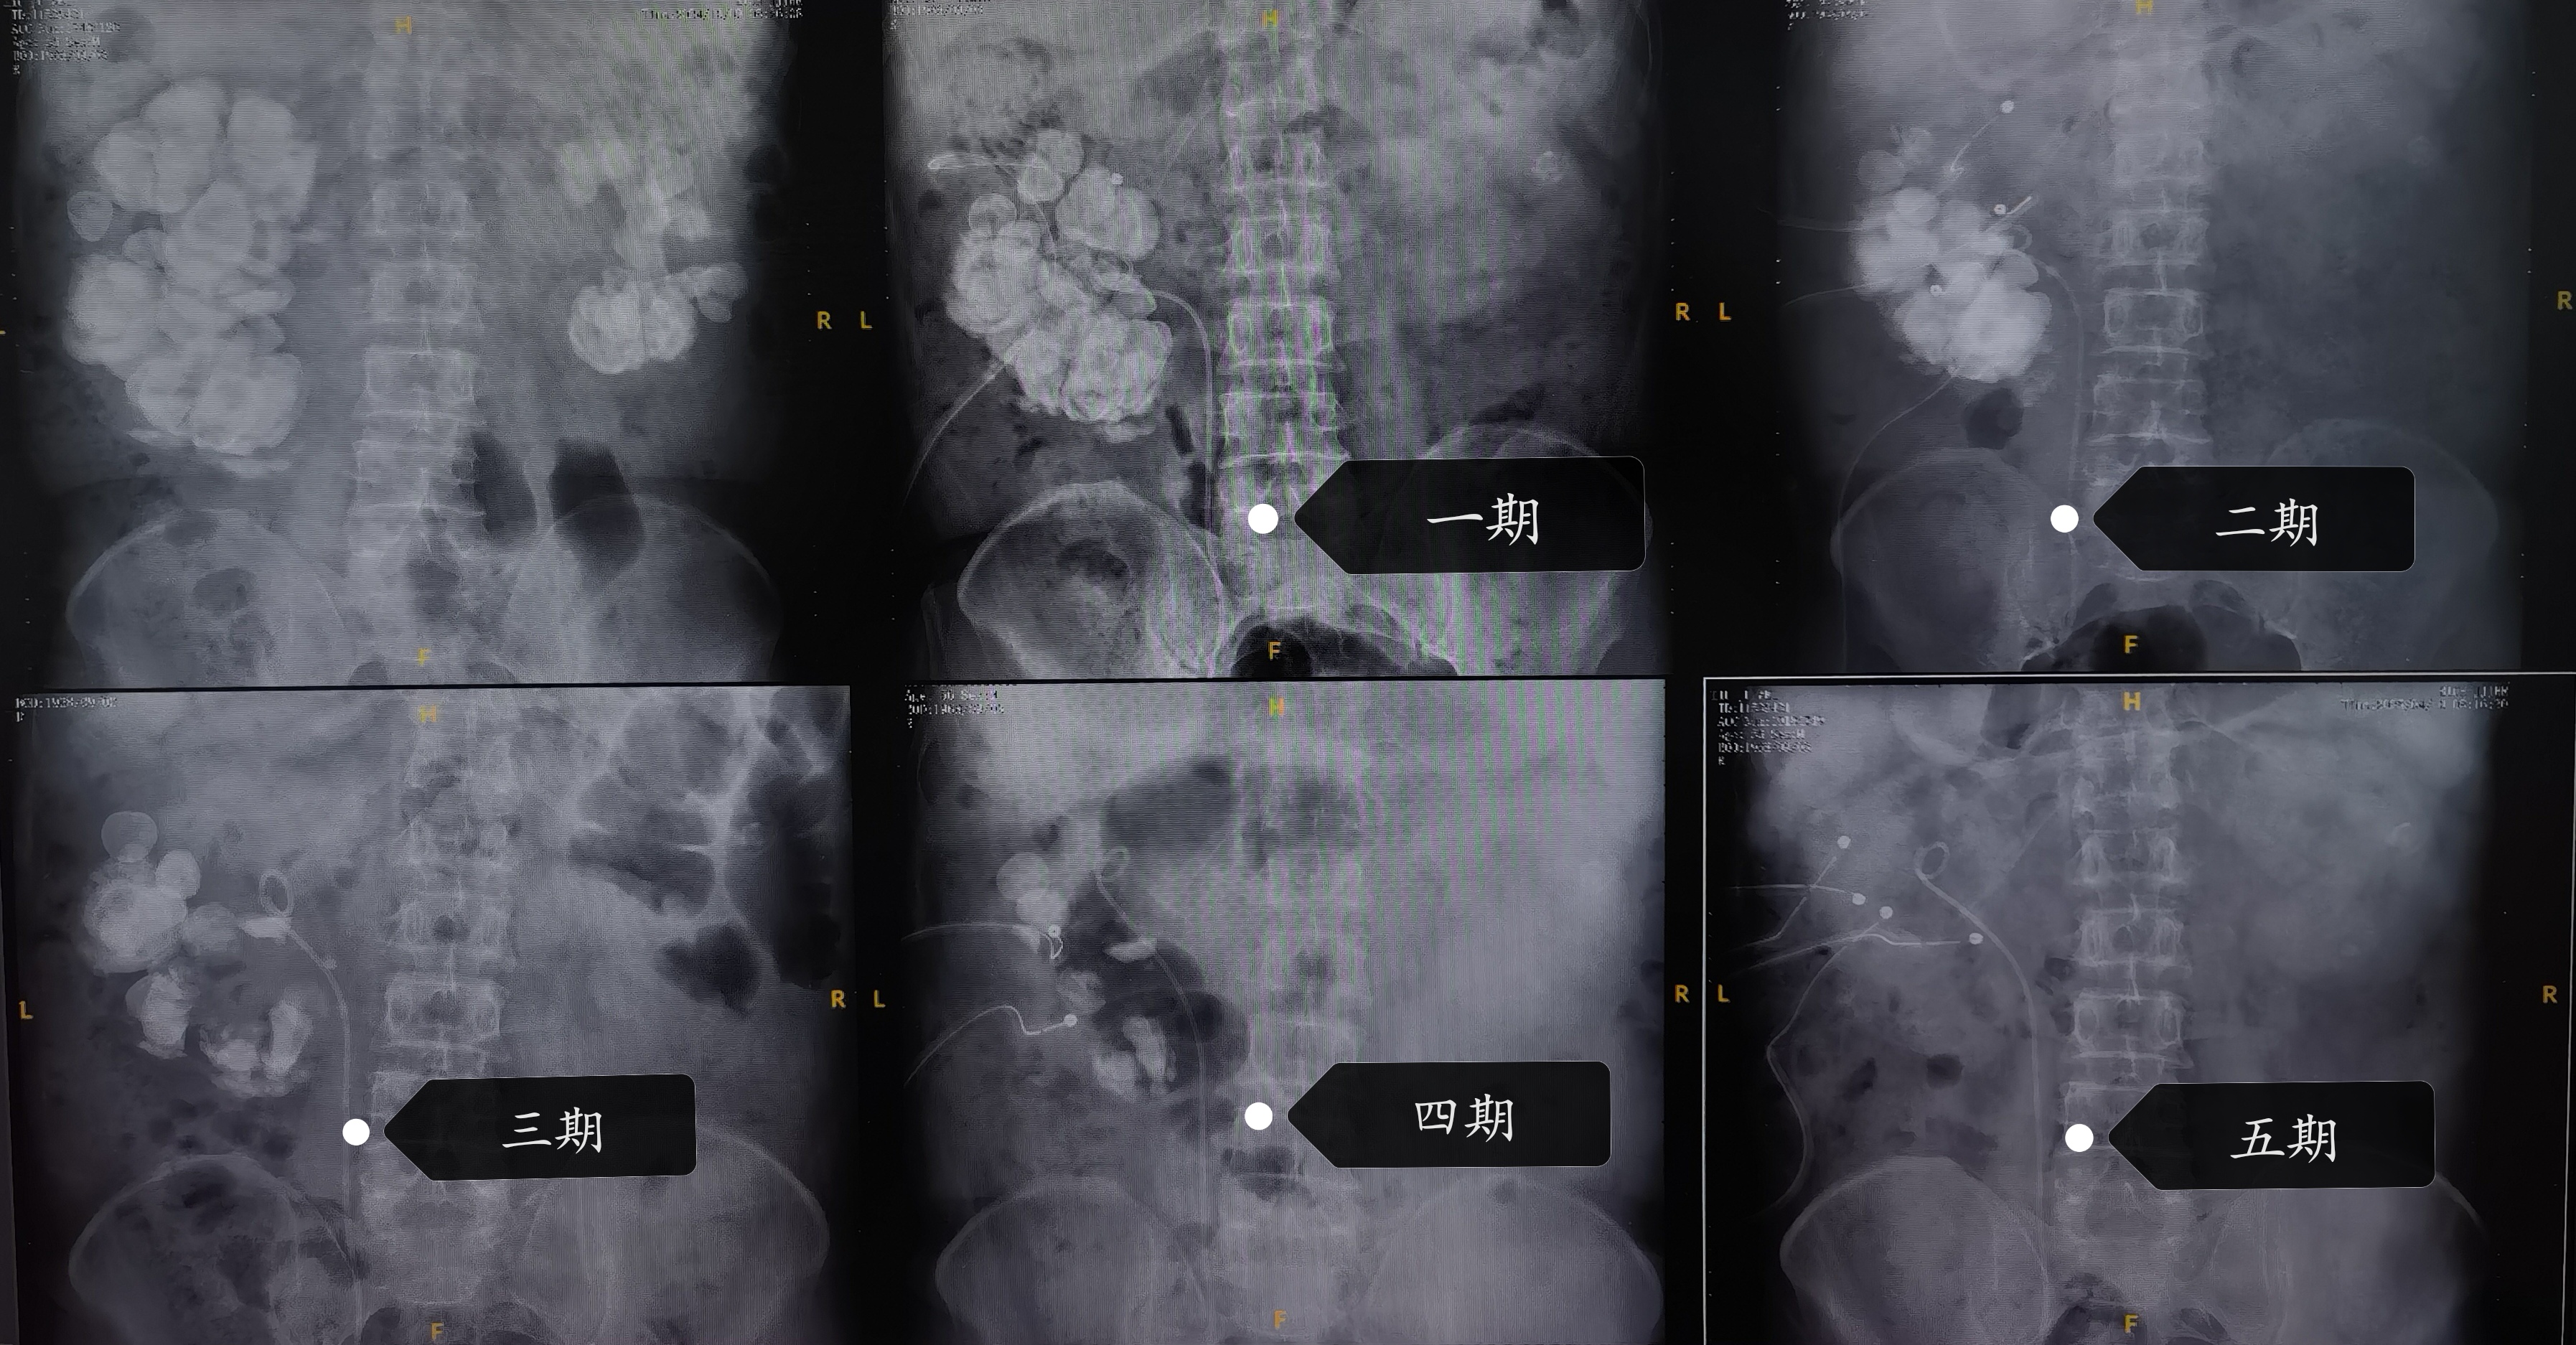

每期术后泌尿系平片对照图

历经半年先后5期手术,最终完整保留住了患者右侧肾脏并清除了右肾的所有结石。术后总肾功能(血肌酐)稳定在150μmol/L(较术前下降90μmol/L),清除结石总重量约1.7斤。